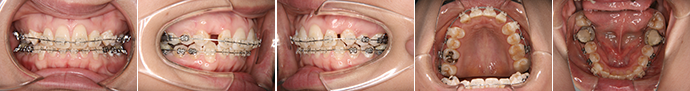

| 主訴 | 上の前歯が出ている、下の前歯がデコボコ |

| 年齢・性別 | 26歳 / 女性 |

| 治療方針 | 顎関節に少し問題があるAngleⅠ級上下顎前突。患者の希望もあり、できるだけ前歯を後退して口元の突出感の改善を行う。 |

| 抜歯部位 | 小臼歯4本抜歯 |

| 使用装置 | ホールディングアーチ、マルチブラケット装置 |

| 治療期間 | 26か月 |

| リテーナー | 上顎インビジブル、下顎スプリングリテーナー |

| 費用 | 825,000円(税別) |